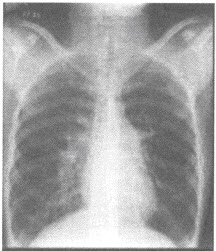

女性,35岁。阵发性劳力性呼吸困难及阵发性夜间呼吸困难。听诊可闻及奔马律。行胸部平片检查如下图:

第1题,共2个问题

(单选题)关于该病在X线透视下的征象下列哪项是正确的()

A:两心缘搏动无明显减弱

B:左心室段搏动区域性减弱

C:右心房段搏动减弱

D:心脏搏动快速有力

E:主动脉结搏动增强

第2题,共2个问题

(单选题)该患者可考虑下列哪种疾病()

A:右室流出道狭窄

B:限制型心肌病

C:扩张型心肌病

D:二尖瓣关闭不全

E:室间隔缺损